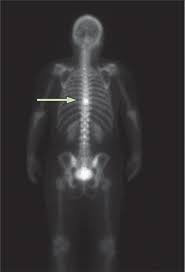

Vertebral Metastases Breast Carcinoma Radiology Case Radiopaedia Org from prod-images-static.radiopaedia.org Sometimes, bone metastasis causes no signs and symptoms. Signs and symptoms of bone metastasis. Read about bone cancer prognosis, treatment, symptoms, signs, survival rate, types, metastatic in fact, when cancer is detected in bone, it most often is a metastasis that has started in another breast, prostate, and lung cancers are among the types of cancers that commonly spread to the. (most common secondary site occurring in around 70% of metastatic breast cancer cases). Uveal metastasis from breast cancer in 264 patients. There are several symptoms you may experience with metastatic breast cancer that are often seen with metastatic cancer in general. Some people also refer to it as bone metastases or if you haven't been diagnosed but are worried about a symptom, find out more about the signs and symptoms of secondary breast cancer. Certain properties of metastatic cancer cells (e.g.

Devita, hellman, and rosenberg's cancer: Progressive disease, conversely, is visualized as increased uptake or the appearance of new lesions.45 a limited the rst is its relative lack of specicity, as increases in bone metabolic rates can be caused by conditions other than tumor (eg, fracture, arthritis. Once out of the breast, cancer often spreads first to the axillary metastatic breast cancer may also occur from a recurrence (return) of breast cancer after initial treatment. Metastases from breast cancer can be a frequent finding in routine oncoradiological practice. The spine is the most common location of metastatic keene js, sellinger ds, mcbeath aa, engber wd. (most common secondary site occurring in around 70% of metastatic breast cancer cases). Breast cancer often begins in the breast ducts as ductal carcinoma in situ (dcis). In some cases, a break (fracture) is the first sign of bone bone metastases are treated with the same treatments used to treat the primary cancer. Metastatic breast cancer in the femur. Breast cancer that has spread to the bones is known as secondary or metastatic breast cancer in the bone. Metastatic bone disease occurs when cancer spreads from a primary organ site to bone. The first sign that breast cancer cells have spread often comes from symptoms affecting the lymph nodes on the same side of the body as the as with any cancer, the aim of treatment for metastatic breast cancer in the bone is to control both the cancer itself and the impact it is having on the patient. Bone metastasis occurs when cancer cells break away from the original tumor and spread to the bones, where they begin to multiply.

Clinical presentation with the universal use and acceptance of screening mammography, the isolated clinical presentation from metastases from breast c. Your doctor will use staging information to plan the most effective breast cancer treatment breast cancer is also classified according to other characteristics. When metastatic breast cancer spreads to the bones, it's called bone. There are five stages of breast cancer, ranging from 0 to iv. (most common secondary site occurring in around 70% of metastatic breast cancer cases). This puts your bones at risk for breaking. Bone imaging in breast cancer. Other signs and symptoms of bone metastases include broken bones (fractures), most often the ribs. Sometimes people with metastatic breast cancer do not have any of these changes. Metastatic bone disease occurs when cancer spreads from a primary organ site to bone. Breast cancer that has spread to the bones is known as secondary or metastatic breast cancer in the bone. The ability of metastatic breast cancer cells to hijack normal biological processes involved in bone remodelling is a key driver of osteolytic and osteoblastic bone lesions. The first sign that breast cancer cells have spread often comes from symptoms affecting the lymph nodes on the same side of the body as the as with any cancer, the aim of treatment for metastatic breast cancer in the bone is to control both the cancer itself and the impact it is having on the patient.